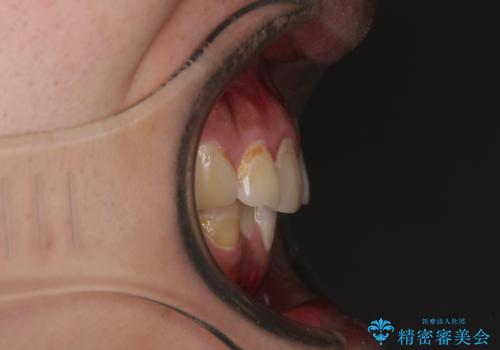

前歯のデコボコ以外に左側の奥歯の咬み合わせに問題がありましたが、価格を抑え、短期間で気になる前歯を治したいとのことでした。

しかし、費用面や期間で悩んでいらっしゃったため、左側臼歯の問題は解決せずに前歯のデコボコのみを改善するシミュレーションを作成し、治療を行うこととしました。

写真より左側臼歯の咬合がタイトではないことが分かりますが、こちらは保定期間に徐々に咬合させていくこととしました。